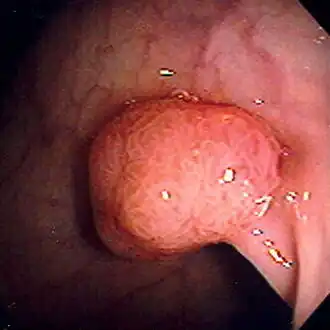

![]() Полип аденоматозной структуры сигмовидной кишки, выявленный во время колоноскопии. Диаметр около 1 см. Удалён диатермической петлей | |

Полип толстой кишки, или колоректальный полип, — это полип (нарост), образующийся на внутренней поверхности ободочной или прямой кишок. Полипы толстой кишки обычно не ассоциируются с какими-либо симптомами. Иногда могут становиться причиной выделения крови с калом. Полипы толстой кишки требуют повышенного внимания из-за вероятности наличия в них злокачественных сегментов и риска перерождения доброкачественных полипов толстой кишки (аденом) через некоторое время в злокачественные новообразования.

По установившейся практике обнаруженные полипы размером до 5 мм удаляются во время колоноскопии при помощи щипцов или петли. В случае, если во время ректороманоскопии или во время какой-либо другой диагностической процедуры были обнаружены аденоматозные полипы, то пациенту придётся пройти и процедуру колоноскопии с последующим удалением аденом в условиях хирургического стационара. Несмотря на то что злокачественные сегменты, как правило, не выявляются в полипах размером менее 2,5 см, удалению подлежат все обнаруженные аденоматозные полипы, чтобы снизить в будущем вероятность образования рака толстой кишки.